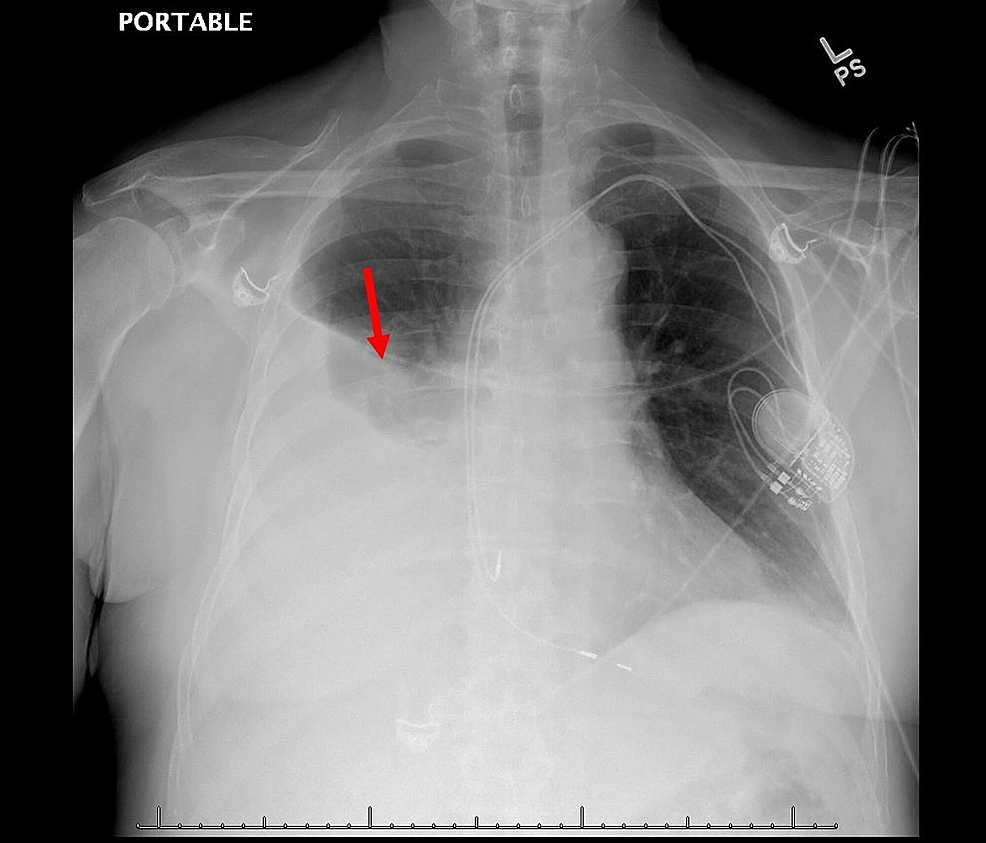

Large Unilateral Pleural Effusion with Pacemakerassociated Post Post Cardiac Injury Syndrome Symptoms Auch erst nach monaten, zu perikarditis, perikarderguss, pleuritis,. Diagnosis and management of persistent precipitating pathologies such as acute coronary syndrome (acs), pulmonary diseases, hemorrhage, sepsis, and various toxidromes. Symptoms of dressler syndrome are likely to start weeks to a few months after a heart attack, surgery or injury to the chest. Post cardiac injury syndromes (pcis) are becoming increasingly common,. Post Cardiac Injury Syndrome Symptoms.

Cureus Large Unilateral Pleural Effusion with Pacemakerassociated Post Cardiac Injury Syndrome Symptoms Symptoms of dressler syndrome are likely to start weeks to a few months after a heart attack, surgery or injury to the chest. Dressler’s syndrome usually occurs within one to six weeks after heart surgery or a heart attack, but it can take up to several months for symptoms. Auch erst nach monaten, zu perikarditis, perikarderguss, pleuritis,. Post cardiac injury. Post Cardiac Injury Syndrome Symptoms.